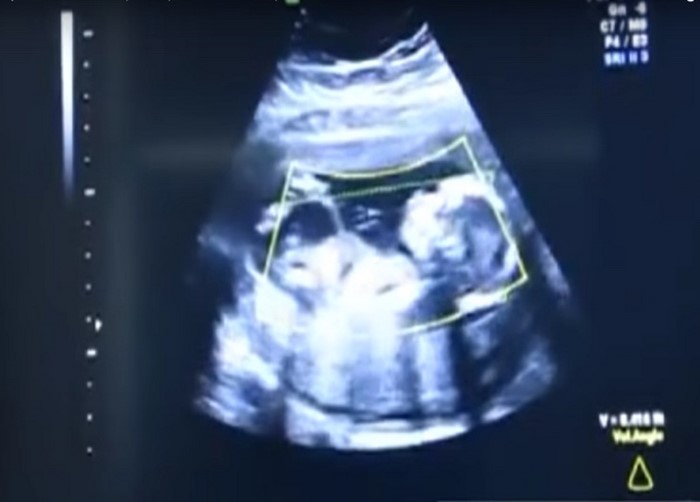

Шарана 41-ші аптаға дейін жатырда емес, құрсақ қуысында біткен. Дәрігерлер бірден әйелге операция жасады. Уақыт өткізіп алса өлімге алып келуі мүмкін еді.

Дәрігерлер әйелдің туылғаннан жатыр мойнының дамуында ақау болған деп болжайды. Эмбрион ағзадағы қалдықты мүшеге жабысып, ол жарылғаннан кейін құрсақ қуысына түскен.